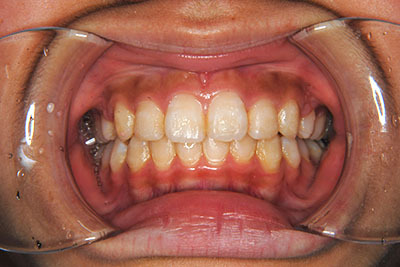

小学生高学年や中高生で矯正治療を考えている方へ

歯が乳歯から永久歯に生え変わった小学生高学年や、中高生でも矯正治療に手遅れということは全くありません。

成長中の顎の骨を矯正できたり、この時期の矯正はおとなになってから矯正治療を始めるよりも短期間で済むことがほとんどです。当院だとおおよそ1年で動的治療(マルチブラケット装置をつける期間)が終わることが多いです。